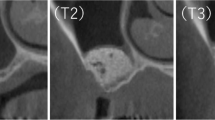

Bone samples were fixed to the scanner compartment of the microCT device (Skyscan 1174, Skyscan, Kontich, Belgium) via patafix. After the area setting of 800 µA, 50 kV, and 40.89 µm pixel size was arranged and saved, each sample was scanned with the same setting. The rotation step of microCT was set at 0.7° and the sample was determined to perform 180° rotation scan with 2300 ms exposure. Raw data were obtained during scanning and subsequent reconstructions of these data were carried out with the software NRecon (NRecon version 1.6.9.4, Skyscan, Kontich, Belgium), provided by the manufacturer. During reconstruction beam hardening, ring artifact reduction, smoothing, and frame averaging were individually adjusted to the optimum value for each sample. As a result of the reconstruction of the raw data, 8-bit gray value images were obtained. Reconstructed images were transferred to CTAn (version 1.13.5.1) software. Using CTAn scan, region of interest (ROI) was drawn within the sample to analyze the 3D microarchitecture of each sample.

From each ROI, the following trabecular microarchitecture parameters were analyzed according to the previously described variables in the literature [20, 21]: (1) bone volume (BV) (mm3), volume of the region segmented as bone; (2) total volume (TV) (mm3), volume of the entire ROI; (3) bone volume fraction (BV/TV) (%), ratio of the bone volume to the total volume of the ROI; (4) bone surface (BS) (mm2), surface of the region segmented as bone; (5) specific bone surface (BS/BV) (mm2/mm3), ratio of the segmented bone surface to the segmented bone volume; (6) bone surface density (BS/TV) (mm2/mm3), ratio of the segmented bone surface to the total volume of the ROI; (7) trabecular thickness (Tb.Th) (mm), mean thickness of the trabeculae in the ROI; (8) trabecular separation (Tb.Sp) (mm), mean distance between trabeculae; (9) trabecular pattern factor (Tb.Pf) (1/mm), which is an inverse connectivity index: the higher it is the trabeculae are less connected; (10) fractal dimension (FD), which indicates the complexity of the specimen surface.

MicroCT allows us to evaluate bone samples in 3D plane and to learn about trabecular microarchitecture of the samples. It is a non-destructive method and gives high-resolution images of bone structure [15]. There are a limited number of studies examining augmented sinus region by microCT in terms of trabecular microarchitecture [16, 24,25,26,27,28,29,30,31,32,33]. In these sinus augmentation studies, heterogeneity exists with respect to the grafting material, healing time, and measured outcomes. Moreover, a detailed discussion of microarchitecture parameters is unavailable. This may be attributed to the evaluation of trabecular microarchitecture being a relatively new area of research for implant surgery. However, the majority of these studies agreed that microCT is effective for evaluating 3D bone structure. Huang et al. [27] evaluated bone microarchitecture by microCT after sinus augmentation with autogenous bone graft and stated that it is important to understand the trabecular remodeling of autogenous bone graft and hereby to determine the implant prognosis in grafted maxillary sinus region. Kühl et al. [16] performed sinus augmentation using different graft materials and evaluated whether microCT is suitable for examining the morphometric structure of healing grafts. Consequently, it was stated that this method is promising.

To the authors’ knowledge, this is the first study that microCT technique has been used to perform a microarchitecture evaluation of bone samples, retrieved from hyaluronic matrix applied maxillary sinuses. Microstructural properties displayed statistically significant difference only for BS/TV parameter between two groups. As a parameter showing bone surface density, BS/TV was higher in hyaluronic matrix group compared with control group. This is a notable result that addition of hyaluronic matrix to xenograft may be an alternative treatment for implant placement in poor bone density areas such as type 4 bone. This result should be confirmed by implant stability and torque analyses at the time of implant placement.